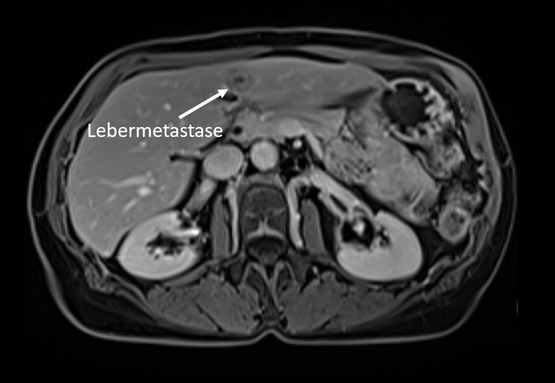

Darstellung einer kleinen Lebermetastase mittels Leber-MRT in der Radiologie Nürnberg.

Darstellung einer kleinen Lebermetastase mittels Leber-MRT in der Radiologie Nürnberg Martha-Maria.

Die Leber befindet sich im Oberbauch und ist das zentrale Organ des Stoffwechsels. Dabei lässt sich die Leber in einen rechten und linken Leberlappen unterteilen. Die häufigsten bösartigen Veränderungen, die man in der Leber findet, entstehen nicht aus Leberzellen, sondern sind Tochtergeschwülste (Metastasen) von anderen bösartigen Erkrankungen wie zum Beispiel Darmkrebs.

Die häufigsten von Leberzellen ausgehenden bösartigen Erkrankungen sind der Leberzellkrebs (Hepatozelluläres Karzinom) und der Gallengangskrebs (Cholangiozelluläres Karzinom). Häufig zeigen sich erst spät Symptome, die allerdings unspezifisch ist. Auch die Leberfunktion ist am Anfang nicht eingeschränkt.

Wie läuft die Leberkrebs-Vorsorge ab?

Daher ist es besonders wichtig, Veränderungen frühzeitig zu erkennen. Insbesondere die MRT kann im Anfangsstadium bereits Raumforderungen in der Leber abbilden und ist der CT zur Beurteilung der Leber überlegen.